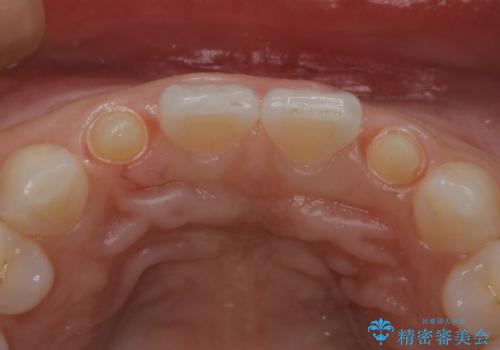

以前使用していた被せ物を除去して、仮歯に置き換えます。

その後、歯の最終的な形を作って型取りを行います。

当院で患者様の口腔内の写真を撮影し技工士さんに指示を出して完成します。